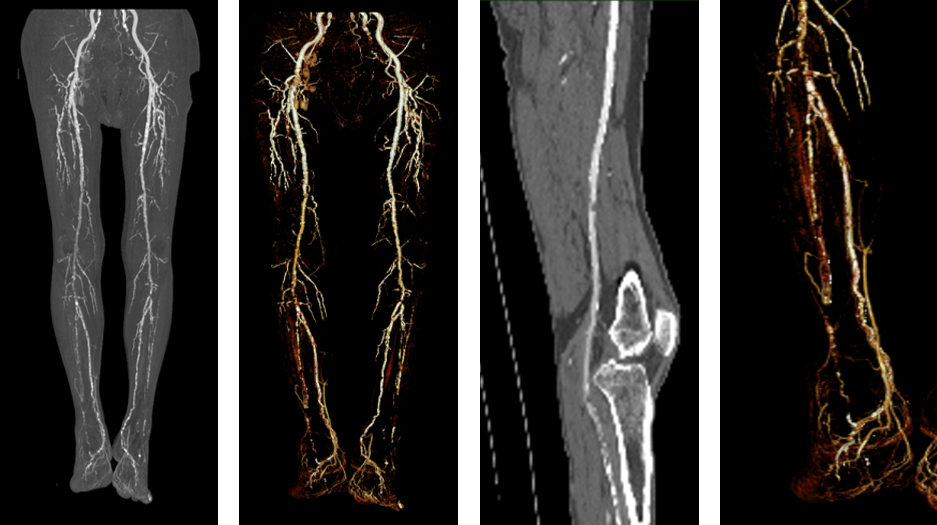

患者为76岁女性,因“血糖升高15年,伴右足溃烂2月”入院。查体:股动脉(左++,右++),腘动脉(左+,右+),胫后动脉(左-,右-),足背动脉(左-,右-)。既往史:糖尿病、高血压。辅助检查:ABI(左0.70,右0.55),下肢动脉彩超显示双下肢动脉硬化伴多发斑块,双侧腓动脉及胫后动脉管径细小,血流纤细。CTA提示膝下三分支病变。

术前影像

根据PLAN评估体系,确定为GLASS Ⅲ期,本例患者的TAP路径为开通胫前动脉血流至第三足趾。

手术过程

术中应用V14导丝配合2×200mm、2.5×250mm、3×200mm SABER球囊(10atm,5min)逐级扩张胫前动脉闭塞段,球囊通过性良好,顺利绕过足弓,打通足底动脉弓。随后成功开通腓动脉,最终通过胫前动脉和腓动脉的分支实现了完整的足底弓显影,造影剂浓染效果满意。术后配合清创和换药,患者伤口按计划愈合,足部功能保留,创面愈合。